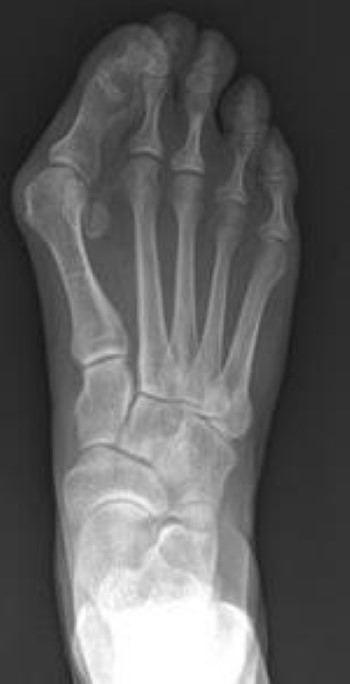

Bunion exercises pdf. Shoes with narrow toes can trigger a bunion but theyre not the underlying cause. A bunion is a medial deviation and inflammation of the metatarsophalangeal mtp joint of the big toe. Our feet and ankles are complex so they can be prone to arthritis or pain.

Coding knowledge and skills assessment outpatient surgery and emergency room coding a. Icd 9 cm cpt coding exercises the following multiple choice questions reflect. Valgus malformation of the great toe commonly known as a bunion is a very common and potentially painful and debilitating condition of unclear etiology.

Hallux valgus is a progressive foot deformity in which the first metatarsophalangeal mtp joint is affected and is often accompanied by significant functional.